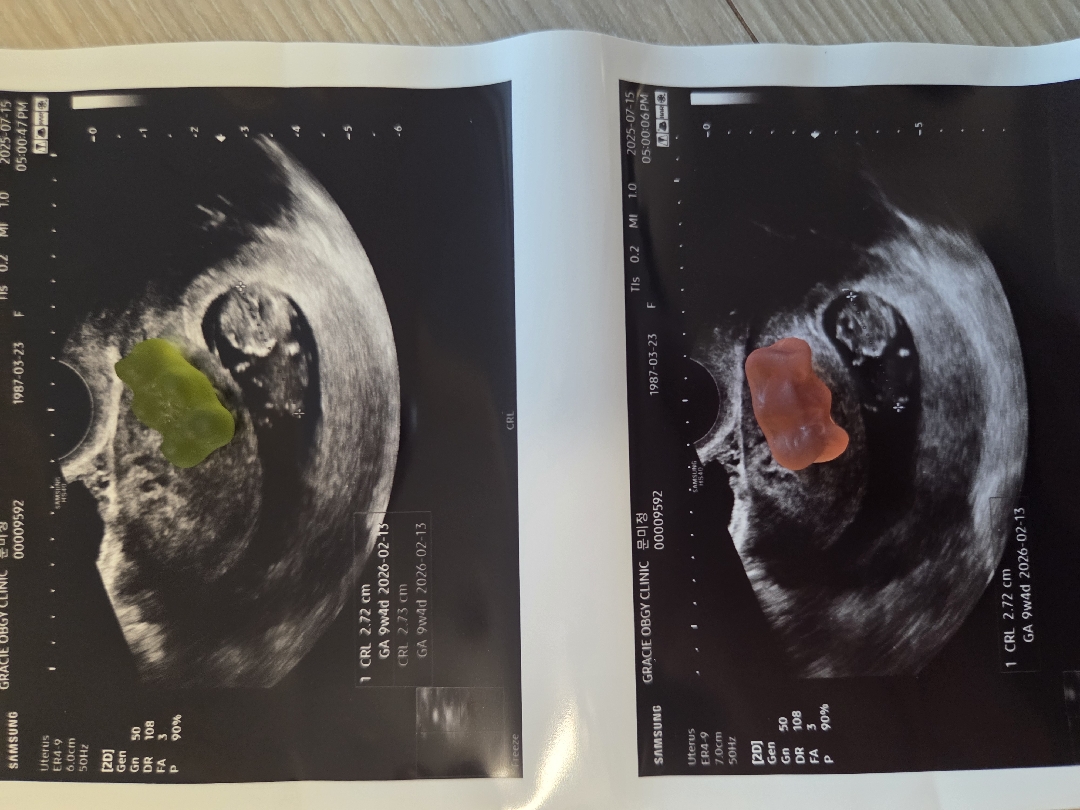

9주4일 하리보

10 주1일차 에 병원검진 예약되어잇는데 하리보 보고파서 집앞 서브병원 다녀왓어요ㅎ 작은게 팔다리도 있고..어찌나 파닥파닥 활발하게 움직이는지..너무 귀엽고 소중해요ㅎ 고맙고 너무 귀여워서 눈물났어요 ㅎ 입덧 심해도 잘견딜수있다 싶어요ㅎ 아가만 건강하다면야